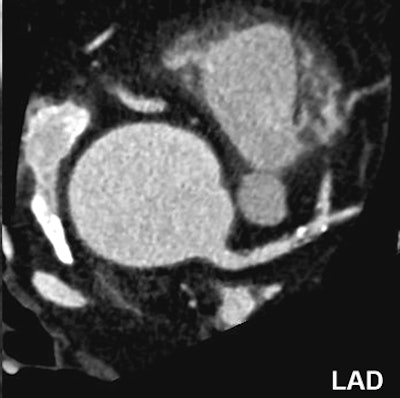

![]() |

| Nonsignificant mixed stenosis of the mid-LAD, false-positive diagnosis with dual-source CT coronary angiography (rated as 60% to 70% stenosis). |